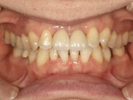

50代女性

![]() |

治療前 |

||

治療中。仮歯。 左上の奥にインプラント埋入。 噛みあわせ治療を行いました |

治療後 全体の歯で食事がおいしくできるようになったと喜んでおられました。 |